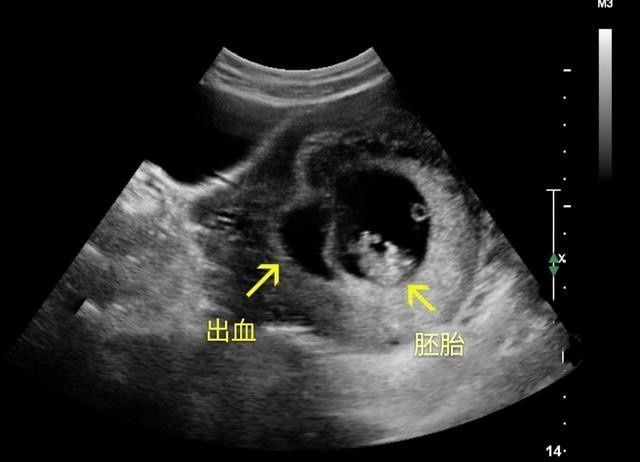

没任何表现的孕妈,就可以等到怀孕12周做产检时,一块儿再产检。

通过B超确定胎儿的实际孕周、检查胎儿的发育情况、看胎儿存在唐氏综合征的风险等。